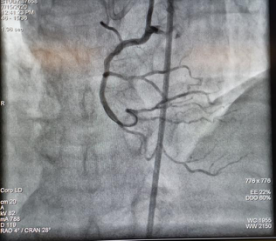

CTO开通前影像 CTO开通后影像